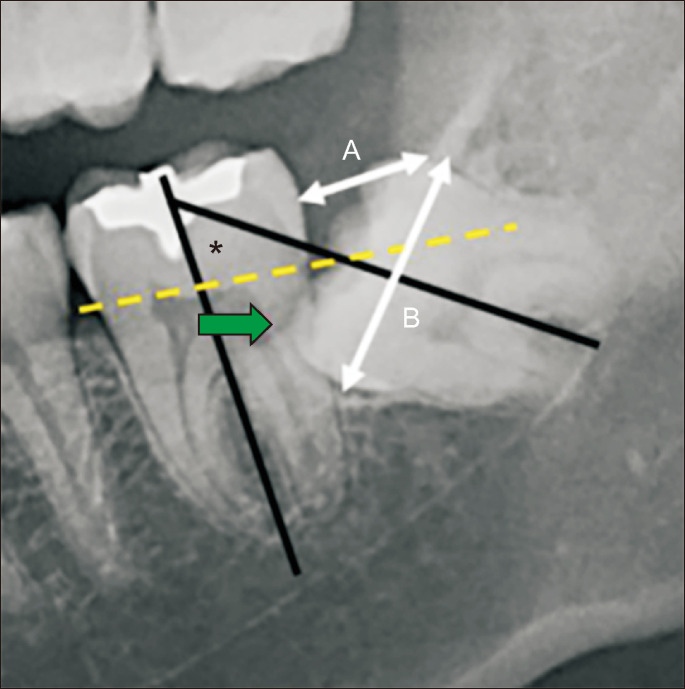

Objectives: : Many three-dimensionally-evaluated difficulty indices for impacted third molars have been suggested; however, their radiological and clinical validation according to the inferior alveolar nerve (IAN) remains unknown. This study aimed to evaluate the association of the difficulty index with IAN proximity and injury risk.

Materials and methods: : We retrospectively enrolled patients with cone-beam computed tomography (CBCT) for a fully impacted mandibular third molar from January to December 2020. We evaluated the third molar according to the difficulty index based on panoramic x-ray and the nerve index based on CBCT and analyzed postoperative nerve complications. The relationships among nerve proximity, difficulty indices, and nerve complications were evaluated. Data were analyzed using the Pearson's chi-square test and the Cochran-Armitage test for trends.

Results: : We included 367 subjects (177 males, 28.9±9.8 years) with follow-up of at least 1 month. Twenty-two subjects had nerve complications. Radiologic evaluation showed that third molars with a high nerve index had an increased difficulty index (P=0.001). Nerve complication risk showed a statistically significant correlation with both nerve and difficulty indices.

Conclusion: : In conclusion, the difficulty index of an impacted third molar was valid in terms of its spatial relationship with the IAN and in predicting nerve complications.